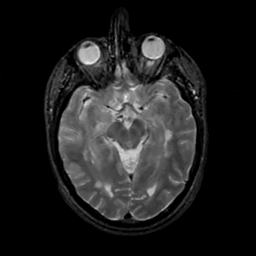

MR Study #14, June 2, 1991 -- Slice #21